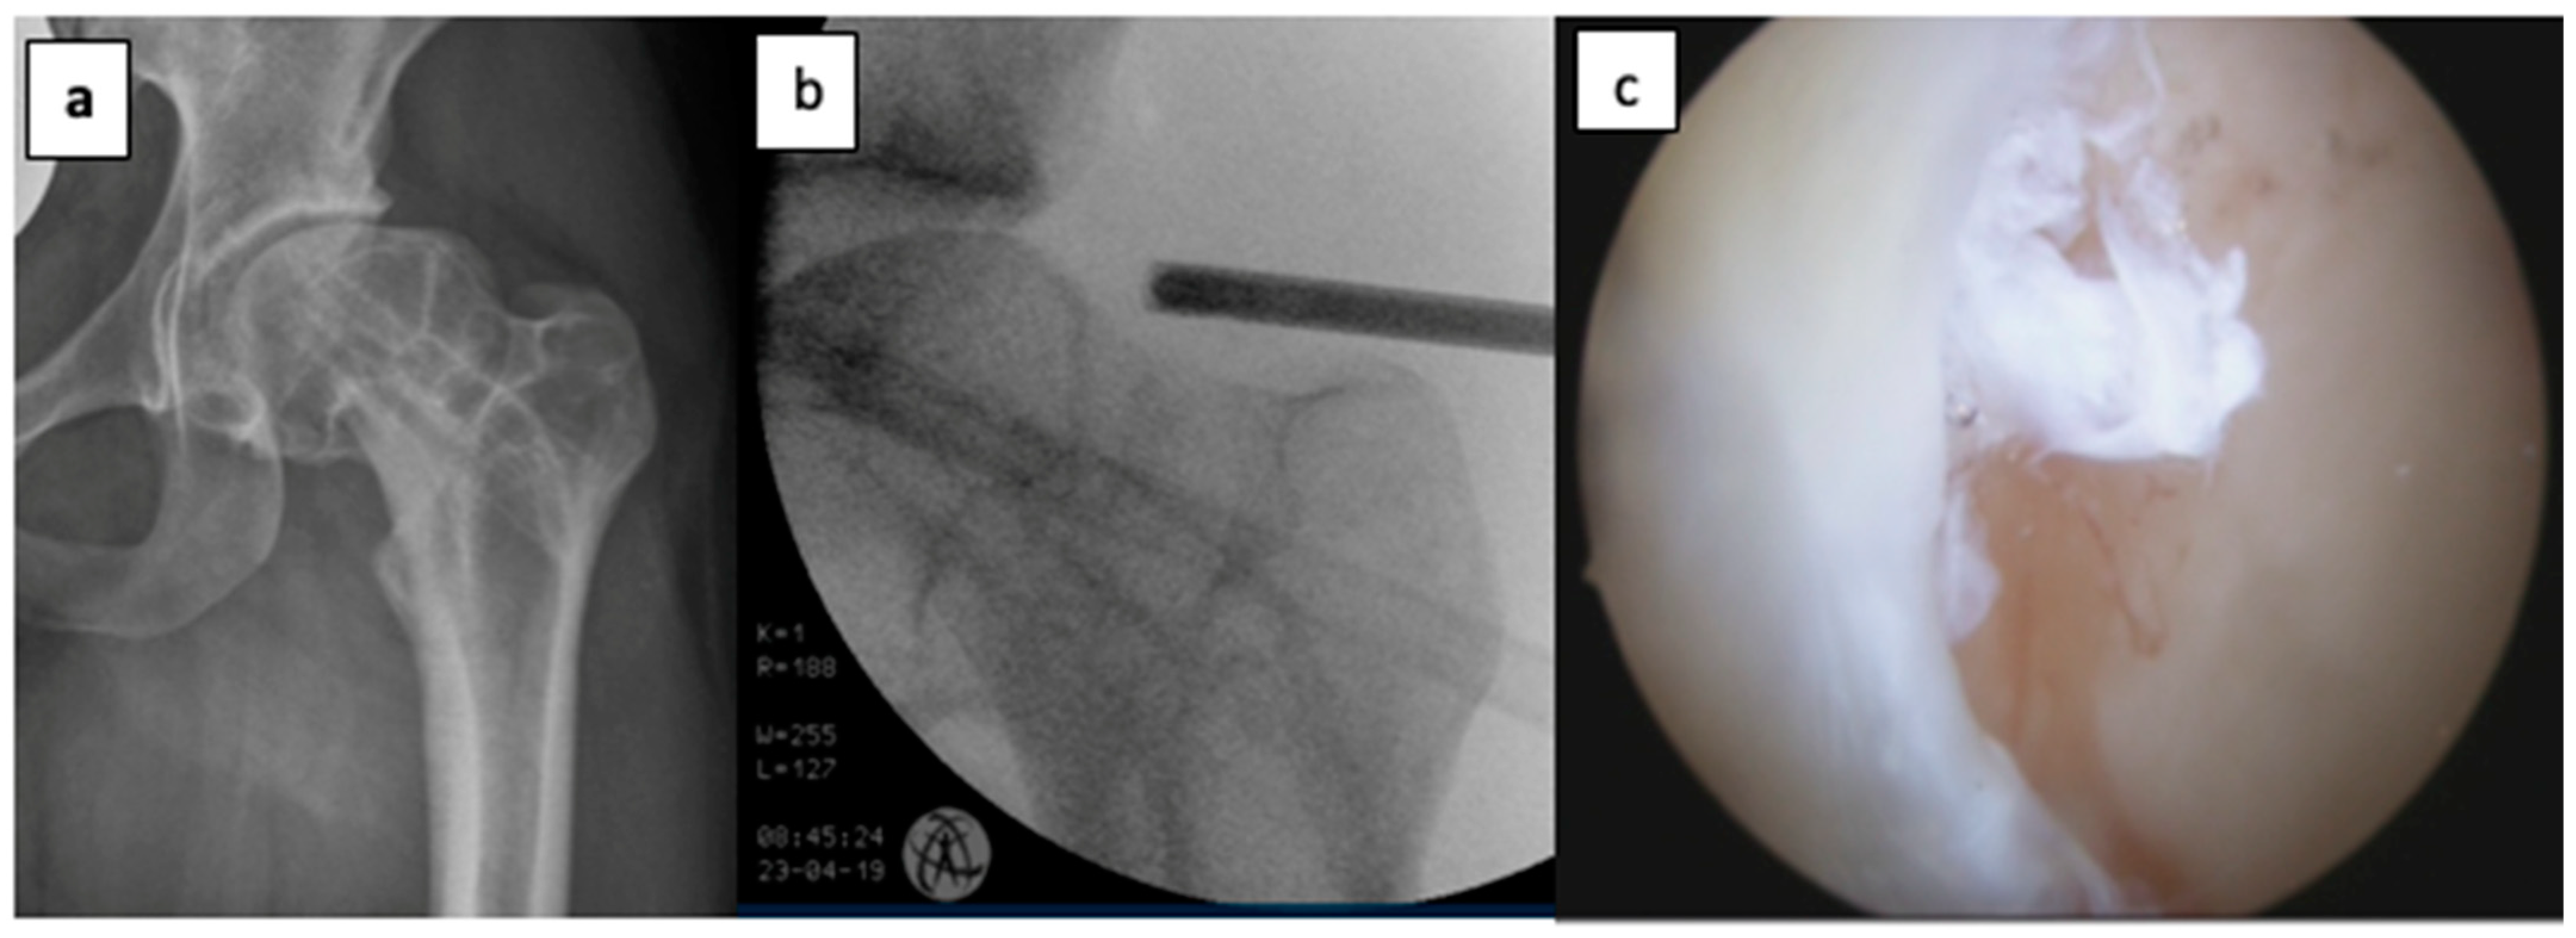

2.2. Indications